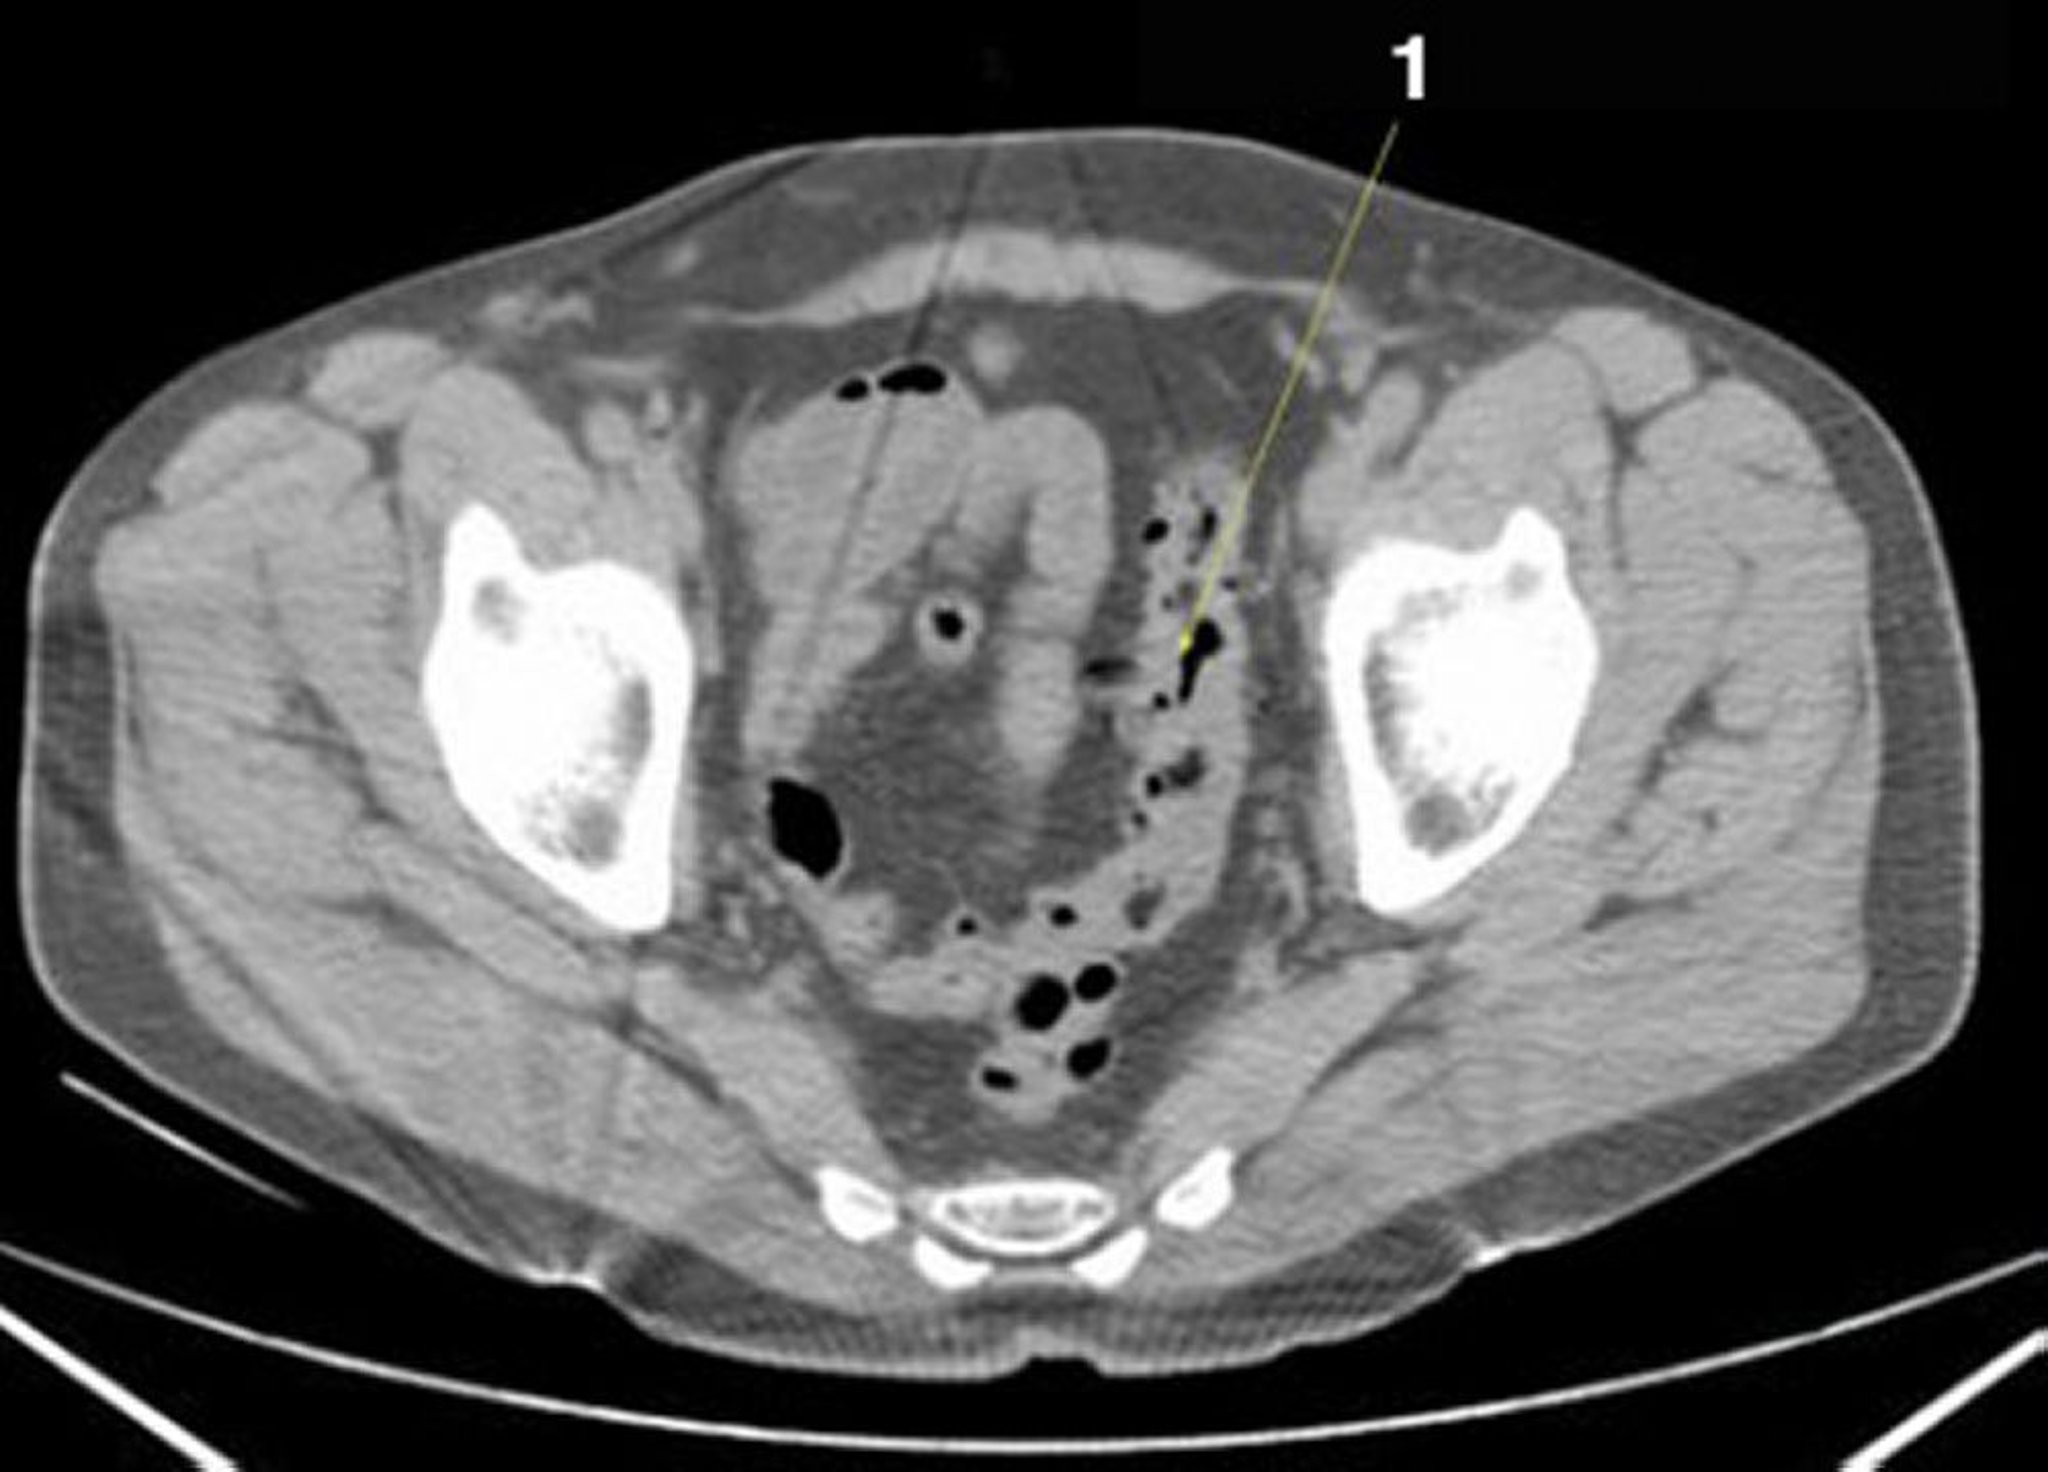

TC senza contrasto dell'addome e della pelvi che mostra un'anatomia normale (Slide 25)

1 = colon sigmoideo.